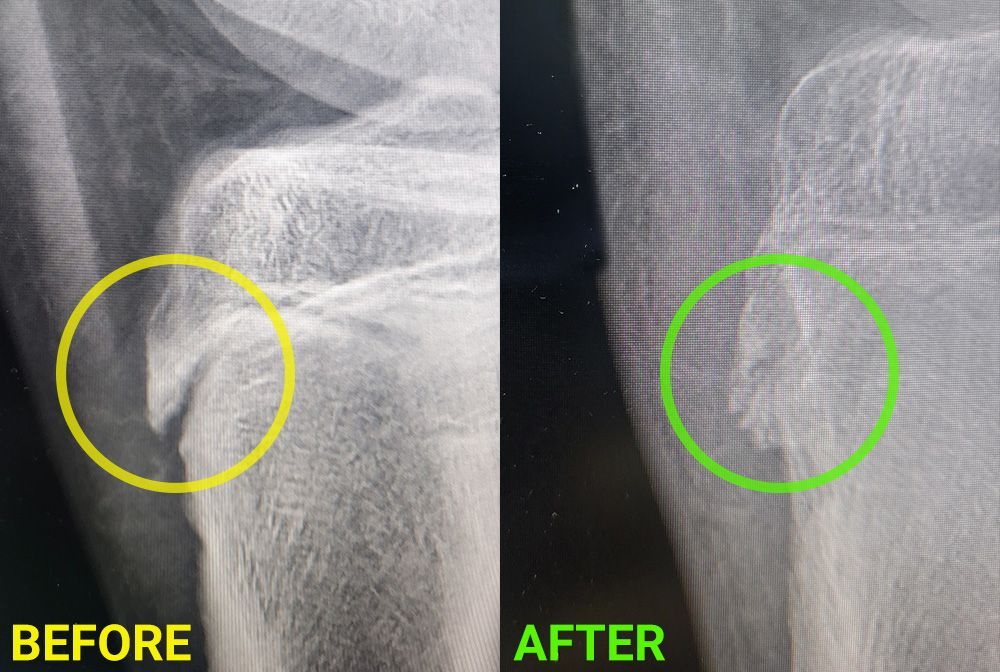

Are you suffering from chronic pain, inflammation, or looking for a non-invasive treatment option? Look no further! Our new Medical MLS Laser Therapy is here to transform your life. This cutting-edge, FDA-cleared Class IV laser technology is designed to provide you with the most advanced laser therapy system available on the market today.

- Faster Healing: Experience accelerated tissue repair and reduced inflammation, allowing your body to heal faster.